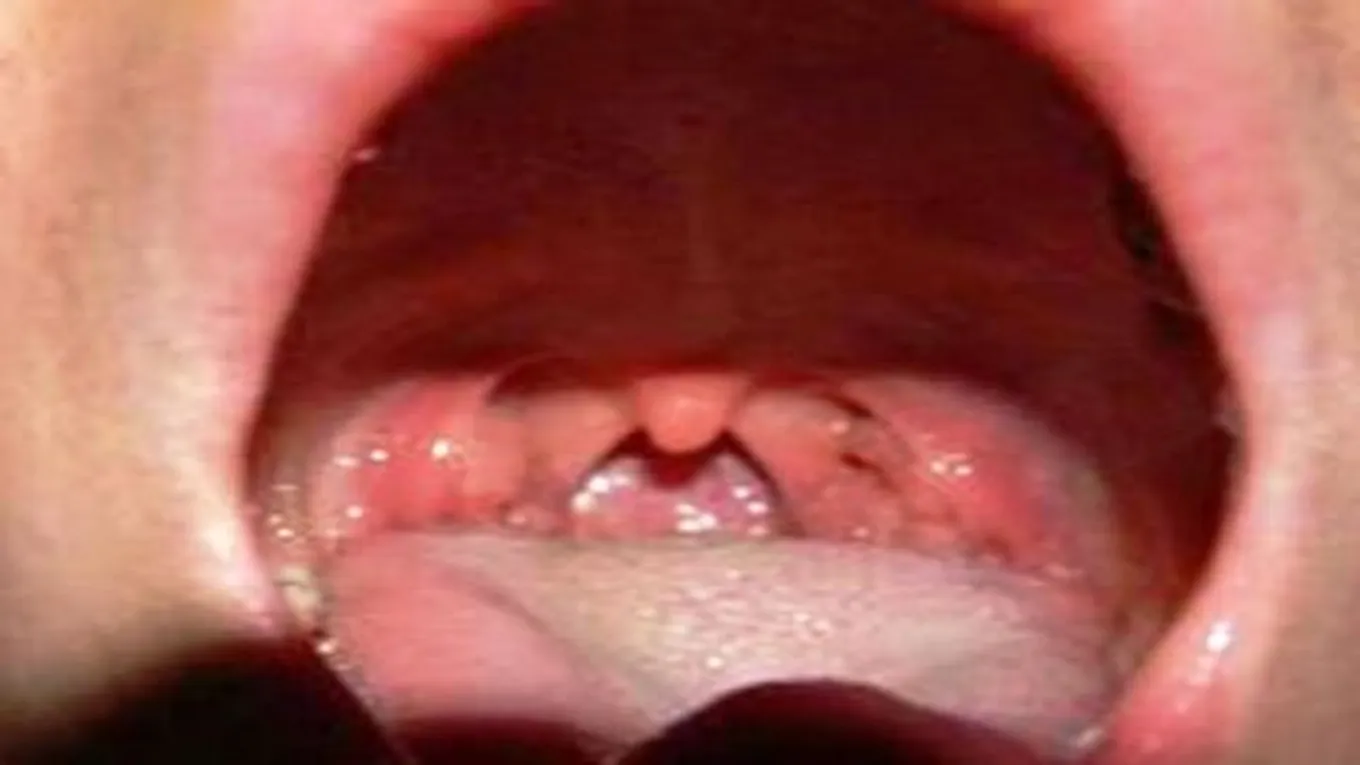

قد يصاب لسان المزمار بالتهاب اسمه التهاب لسان المزمار، وهو من الحالات الطبيّة الطارئة؛ فقد يؤدّي إلى الموت إذا لم يتم العلاج فوراً، وكما ذكرنا سابقاً عن وظيفته في منع الأكل من الدخول الى القصبات الهوائيّة، فإذا حدث الالتهاب به يتورّم ويؤدّي الى عرقلة دخول الطعام إلى الجهاز الهضمي، وقد يؤدّي إلى انسداد الجهاز التنفّسي، ويحدث التهاب لسان المزمار بعدوى في الجهاز التنفّسي أو التعرّض إلى مواد كيميائيّة أو صدمات خارجيّة عليه، ويبدأ التهاب لسان المزمار على شكل تورّم بين جذر اللسان ولسان المزمار، وقديماً كان الأطفال الصغار هم الأكثر تعرّضاً لالتهاب لسان المزمار، وسبب ذلك قصر قطر لسان المزمار لديهم بالمقارنة مع الانتفاخ في القصبات الهوائيّة، ولكن في سنة 1985م تمّ إعطاء تطعيم يُسمّى بتطعيم ضد المستديمة النزليّة؛ حيث إنّه بعد ذلك انخفض حدوث الالتهاب بصورة كبيرة، وكان يصيب الأطفال ما بين (2-4) سنوات، أمّا الأطفال دون هذا السن فلم تحدث لديهم إصابات بهذا الالتهاب.[2]

- يكون لسان المزمار في غير مكانه الطبيعي؛ بحيث إنّه يكون عائداً إلى الخلف، ممّا يؤدّي إلى انسداد مجاري التنفّس، ثمّ الاختناق والوفاة.

- تشكّل خرّاج جيوب العدوى، أو خروج صديد غير معروف الأسباب.